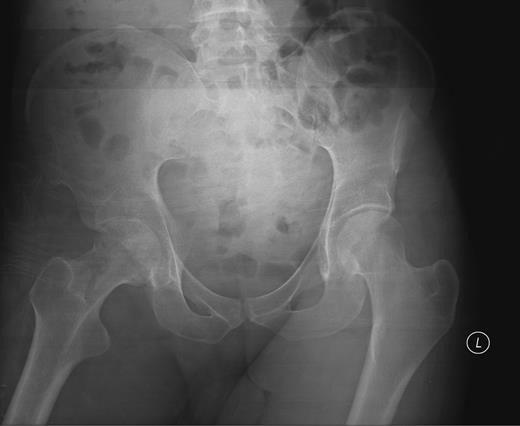

At presentation the patient was afebrile and haemodynamically stable. He was assessed by both the medical and surgical teams at a district general hospital and commenced on intravenous metronidazole and flucloxacillin for a presumed groin abscess. On examination, a pansystolic murmur was heard across precordium with no peripheral stigmata of endocarditis and a discharging sinus in the right groin with a grossly limited range of movement of the right hip. Blood tests revealed a white cell count (WCC) of 7.1 (neutrophils 5.8) and C-reactive protein (CRP) of 146. A pelvic radiograph revealed evidence of degenerative change in the right hip (Fig. 1) and following review by the local orthopaedic team an MRI was carried out confirming avascular necrosis of the right femoral head with an associated collection (Fig. 2).

Pelvic X-ray showing joint space narrowing and collapse of the right hip.